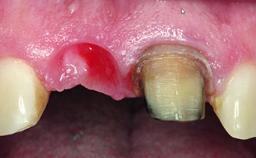

A 23-year-old female, healthy and non-smoking patient had had tooth 11 temporarily restored following a trauma in adolescence. As the patient’s growth had since come to an end and the crown had fractured, she requested an implant-supported restoration of tooth 11. Moreover, the contralateral tooth 21 presented an old composite restoration at the mesial incisal edge. The periodontal tissues were healthy with periodontal probing depth values below 3 mm, but some inflammation was observed around the semi-submerged root of tooth 11.